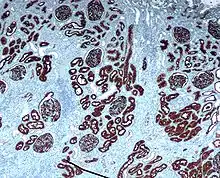

Імуногістохімія або ІГХ — аналітичний метод визначення протеїнів (антигенів) у клітинах біологічних тканин на основі реакції антиген-антитіло.[1] Не слід плутати ІГХ з імуноцитохімією, де той самий принцип застосовують для визначення епітопів в окремих клітинах. Засновниками імуногістохімічного методу є група дослідників під керівництвом Альберта Кунса (Albert Coons), які в 1941 р. вперше отримали мічені флюоресцеїном антитіла та використали їх на практиці.[2] Розробка Кохлером і Мілстейном (1975) гібридомної технології стала кардинальною подією в імуногістохімії, що дозволила отримувати високоспецифічні антитіла у великих обсягах, та дала можливість використовувати імуногістохімію у рутинній клінічній практиці.

ІГХ можна проводити на свіжезаморожених зразках або, найчастіше, на фіксованих в формаліні та залитих у парафінові блоки тканини. Залиту в парафіні тканину мікротом нарізує у тонкий шар (4-5 мкм), якого зафіксовують на скельці для проведення подальших етапів ІГХ.

ІГХ можна проводити прямим або непрямим методами. При прямому методі використовують лише первинні антитіла, мічені хромогенними або флуоресцентними репортерами для їх візуалізації. Використовують рідко, оскільки в цьому випадку отриманий сигнал може бути досить слабким. Непрямий метод дозволяє посилити сигнал від комплексів антиген-антитіло за допомогою застосування додаткових реагентів, зокрема вторинних антитіл.

Специфічно зв'язуються з комплексом первинне антитіло+антиген у досліджуваній тканині. Вторинні антитіла мають у своїй структурі ферменти (пероксидаза хріну, лужна фосфатаза), завдяки яким комплекс антиген-антитіло-вторинне антитіло може бути візуалізований при реакції з хромогенним субстратом (діамінобензидин, BCIP тощо).